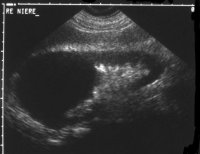

Diagnose und Behandlung von komplexen renalen Zysten bzw. unklaren Befunden umfassen eine Kombination von Sonographie, Urographie und CT (Abbildung 1). Dadurch soll eine Abgrenzung zwischen gutartigen und bösartigen Veränderungen erfolgen.